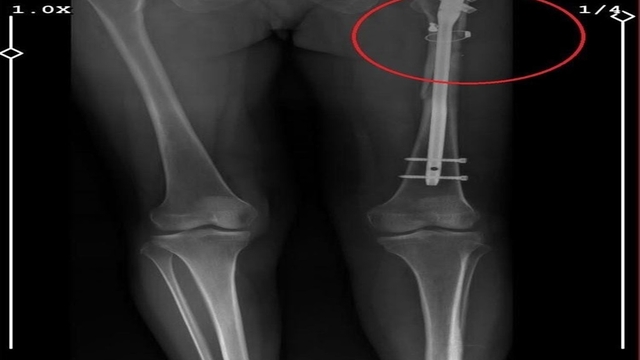

İlyas Sarıkaya, sevgilisi Fatma O.'yu da 8 kurşunla vurup, yaraladı. Arkadaşı Özaslan'ın cesedini önce çarşafa sonra da streç filme sarıp bantlayan Sarıkaya, eczaneden aldığı sargı bezi ve ilaçlarla pansumanını yaptığı sevgilisine yaralı haldeyken 21 gün boyunca cinsel saldırıda bulundu.